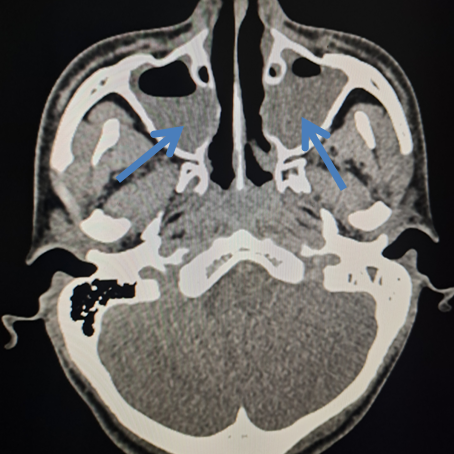

双侧上颌窦炎能自愈吗

1、左侧上颌窦炎的治疗方法主要取决于病情的严重程度以下是针对左侧上颌窦炎的几种主要处理方式增强免疫力如果左侧上颌窦炎仅是单纯的黏膜肥厚,且没有脓液聚积,可以通过增强免疫力来达到自愈的目的具体措施包括锻炼身体和改善饮食...